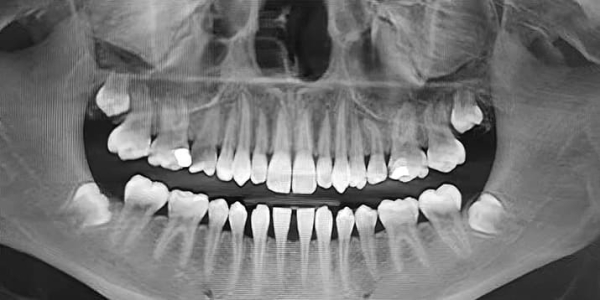

В ходе своего выступления Яков Тимчук представил снимки пациентов из клинической практики с различным расположением зачатков «восьмерок», требующих разной врачебной тактики.

— На ортопантомограмме (см. рис. 2) видно, что зачатки третьих премоляров заложены глубоко, зачатки зубов 1.8 и 2.8 расположены близко к верхнечелюстным пазухам, 4.8 — к нижнечелюстному каналу. Чтобы удалить такие зубы, требуется весьма сложное травматичное вмешательство, как правило, под общим наркозом. При этом показаний для удаления нет, — прокомментировал Яков Тимчук.

Рисунок 2. Ортопантомограмма 15-летнего пациента с глубоко заложенными зачатками 8-х зубов.

— Вот еще один пациент (см. рис. 3) с верхними «восьмерками», залегающими очень близко к верхнечелюстным пазухам, что несет большие риски при удалении. Иногда на удаление направляют пациентов с начинающими прорезываться «восьмерками», при этом показания к удалению отсутствуют, т. е. третьи моляры не препятствуют дистализации (см. рис. 4).

Рисунок 3. Ортопантомограмма 15-летнего пациента с глубоко заложенными зачатками 8-х зубов.

Рисунок 4. Ортопантомограмма пациентки 15 лет. Показаний к удалению «восьмерок» нет.